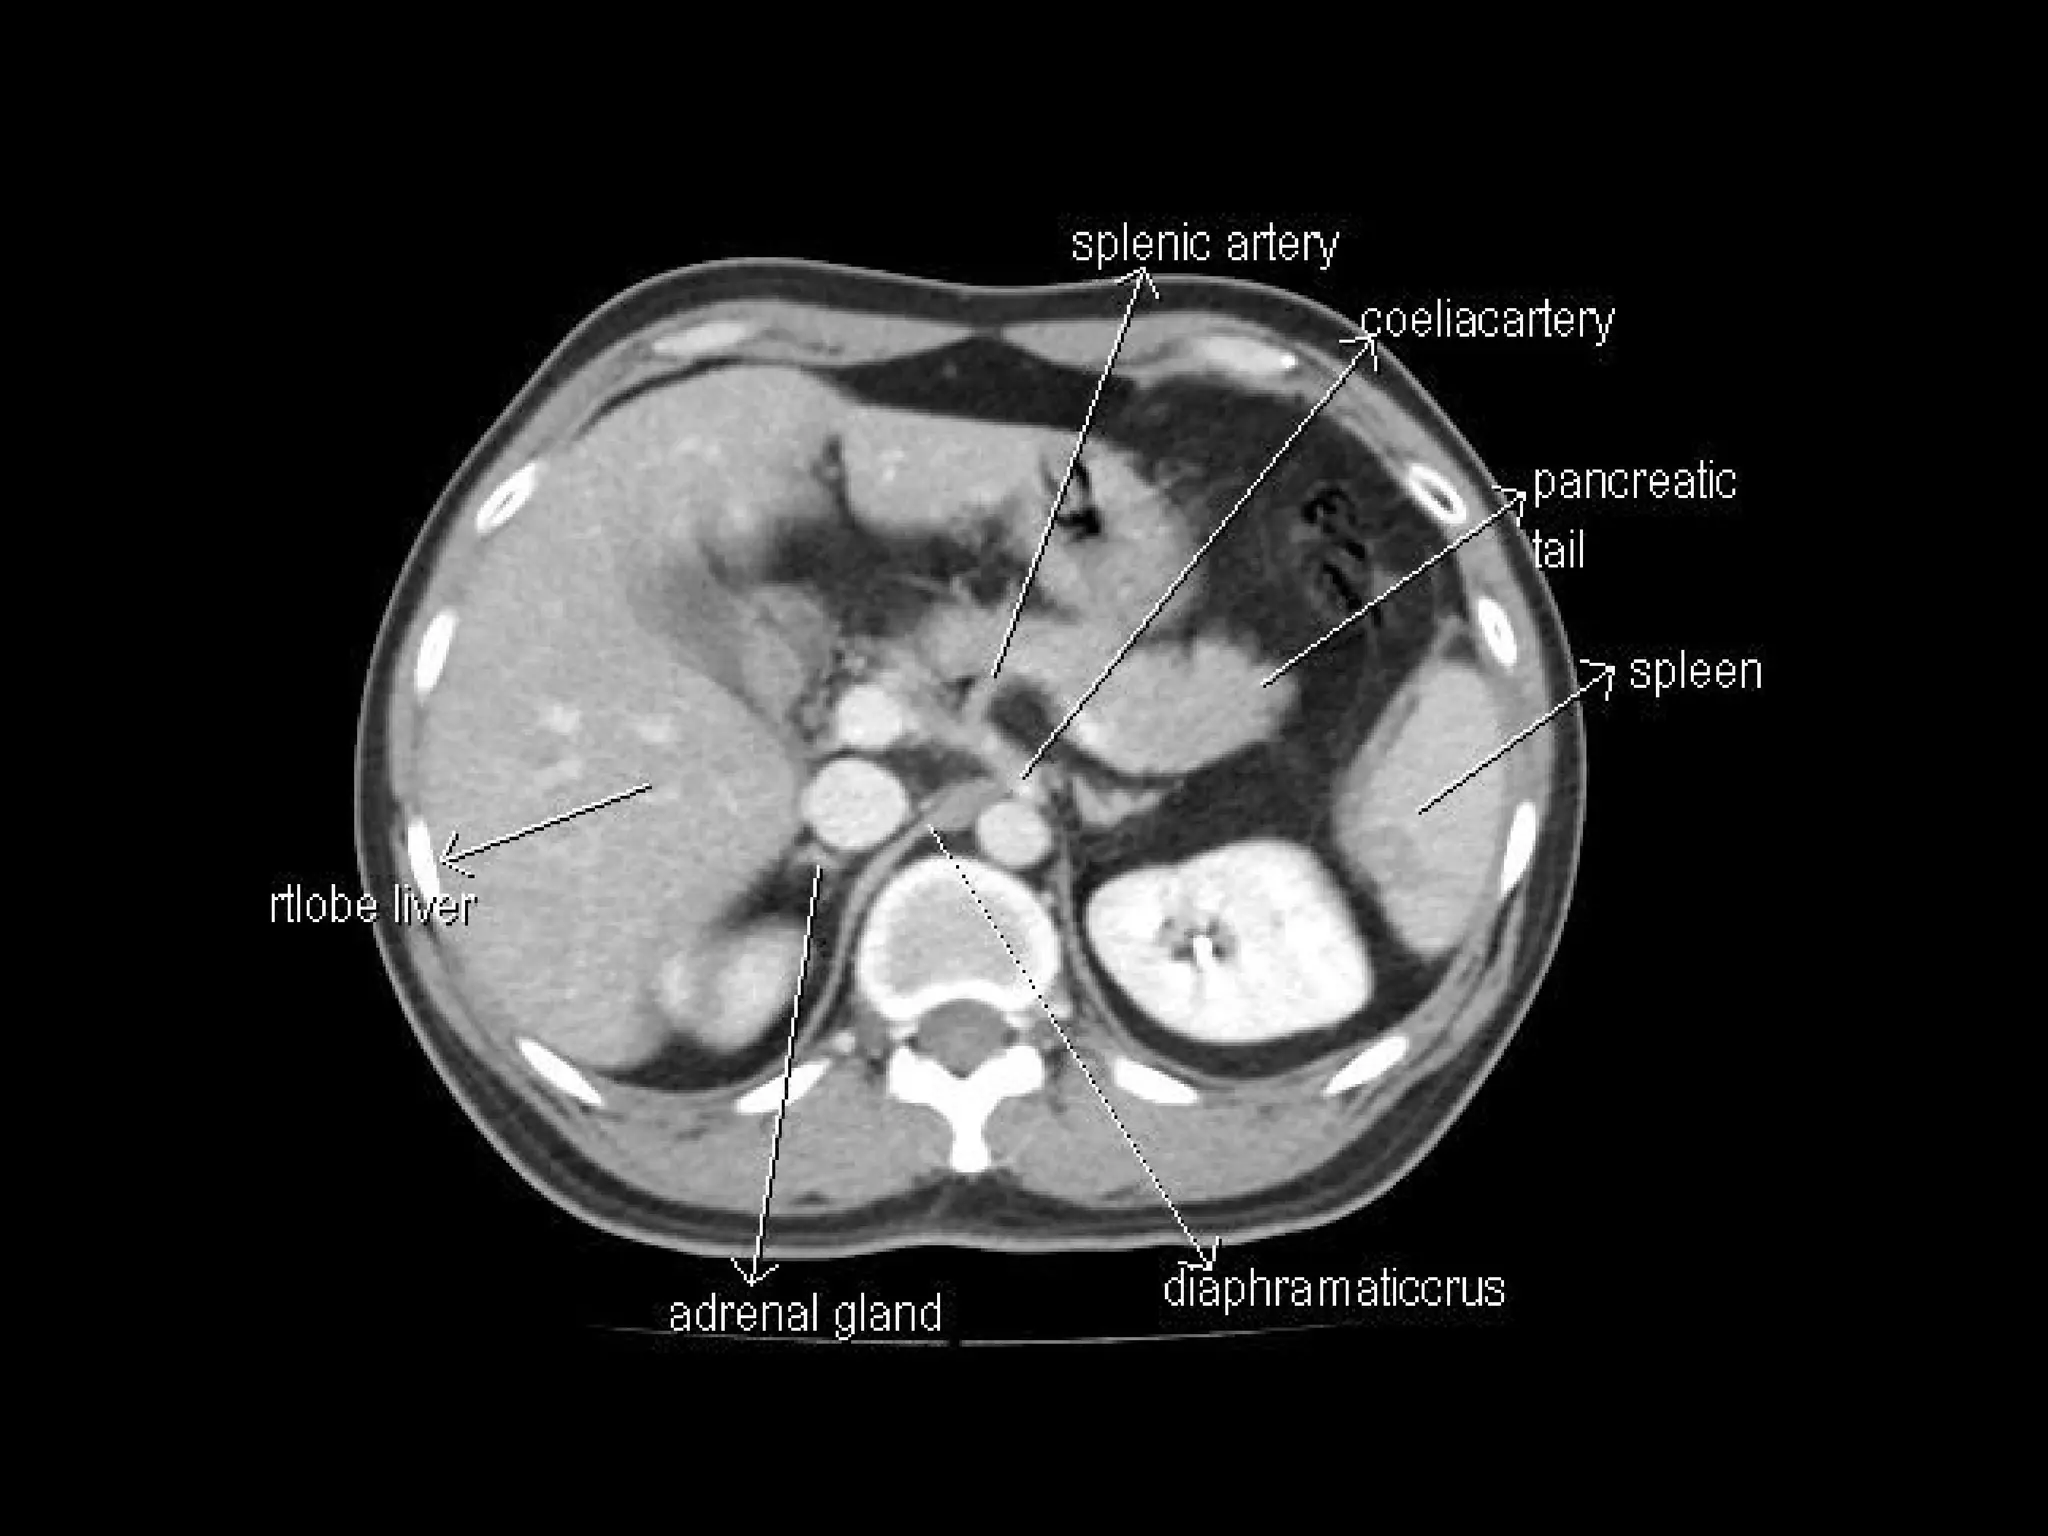

Radiographers are medical professionals who perform diagnostic imaging examinations and procedures to help physicians diagnose and treat diseases. They work under the supervision of radiologists to operate X-ray, CT, MRI, ultrasound and other medical imaging equipment and must have a strong understanding of human anatomy and pathology. Radiographers are responsible for correctly positioning patients, ensuring proper imaging techniques are used, and evaluating the quality of the resulting images.